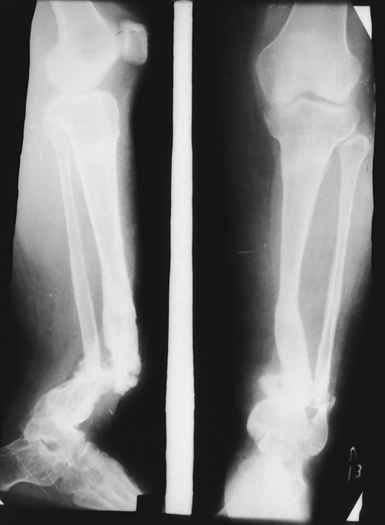

Глубокоуважаемые коллеги женщины! Поздравляем с праздником ВЕСНЫ, Международным женским днем - 8- МАРТА, здоровья , благополучия и успехов во всем! Ребенок 1г, мальчик, от первой беременности, родился без патологии весом 4кг, родители травму исключают, постепенно заметили деформацию н/з голени, которая начала увеличиваться . Брак родственный. Об-но; имеется угловая деформация открытым углом кзади на уровне н/з голени, ригидная , коррекции поддается мало. Функция коленного и г/с суставов не нарушены. Уважаемые детские ортопеды! Почему такое упорное молчание ортопедов! Я искреннее прошу прошения , если можно , мы нуждаемся в Ваших советах! План лечения; этапное, дистракционный аппарат, коррекция деформации, остеотомия в/з б/б кости, удлиняющая дистракция в обл остеотомии с одновременной компрессией в обл псевдоартроза и наблюдение , дальше по обстоятельству Вопросы; . 1. В каком возрасте можно начинать лечение, какие еще варианты лечения? 2. На Р-грамме как будто имеется недоразвитие дистального эпиметафиза м/берцовой кости, тогда что можно делать? С уважением Абдурашид.

Случай, который я представляю, был сделан мной около 20 лет назад в Кургане.

Женщина 28 лет, пошедшая 13 предыдущих оперативных вмешательств по-поводу ВПБ имела 9 см. укорочения.

На первом этапе аппаратом Илизарова закрыто устранена деформация голени.

На втором этапе произведёно освежение краёв костных фрагментов б/б и м/б костей с приданием проксимальному фрагменту б/б кости впалой, а дистальному выпуклой формы, открытие канала проксимального фрагмента и погружной остеосинтез, а также остеотомия б/б кости в в/3 и м/б кости на границе с/3 и н/3 голени. Больной проводился одновременный бифокальный компрессионно-дистракционный остеосинтез. Достигнуто 11 см. удлинение и сращение ВПГ.